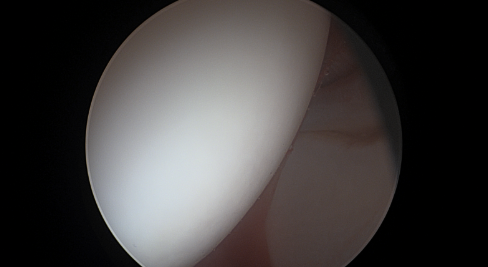

Η γωνία άλφα αποτελεί ένα ποσοτικό χαρακτηριστικό της μηροκοτυλιαίας πρόσκρουσης τύπου cam, σε περιπτώσεις ασθενών με χρόνιο πόνο στο ισχίο. Ωστόσο, τα όρια της γωνίας αυτής αποτελούν ακόμα ένα...